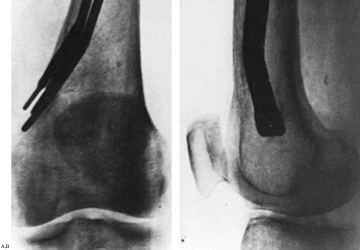

for fixation of intertrochanteric fractures. These devices are placed

retrograde from entry sites near the knee using percutaneous technique

under fluoroscopic control. Theoretical advantages include the

decreased bending moment on the device as previously described for the

Gamma nail; elastic fixation, which was proposed to aid fracture

healing; and percutaneous technique, which hastened fracture union by

preserving the blood supply to the fracture and decreased operating

time and blood loss. In spite of early reports of high rates of

success, later series showed a high incidence of varus deformity and

knee pain caused by the distal migration of pins (121,130).

This led to a high incidence of reoperation for pin extraction and

correction of deformity, which was a problem in elderly patients.

Shortening and external rotation were problems in many of those who

otherwise healed uneventfully. This has led most authorities to

recommend abandoning these devices for fixation of intertrochanteric

fractures. However, some surgeons believe that there is still a place

for Ender nails in the elderly debilitated patient who has a stable

fracture and who can tolerate only minimal operative intervention. The